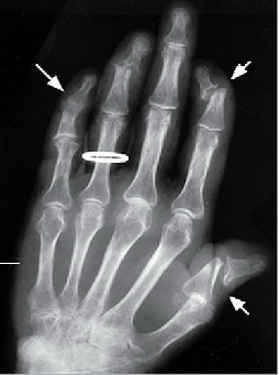

Hình ảnh tổn thương trong bệnh viêm khớp vẩy nến.

Biểu hiện tại khớp có thể nhẹ hoặc rất nặng, hay gặp là sưng, đau, cứng khớp, không đối xứng một vài khớp, điển hình là ở khớp ngón tay; một số ít có viêm nhiều khớp đối xứng hoặc chủ yếu là đau, hạn chế vận động ở cột sống và khớp cùng chậu tùy theo thể lâm sàng. Ngón tay, ngón chân bị sưng toàn bộ một hoặc vài ngón tay hoặc ngón chân (chân hay gặp hơn tay), gặp ở 1/3, thậm chí 1/2 bệnh nhân.